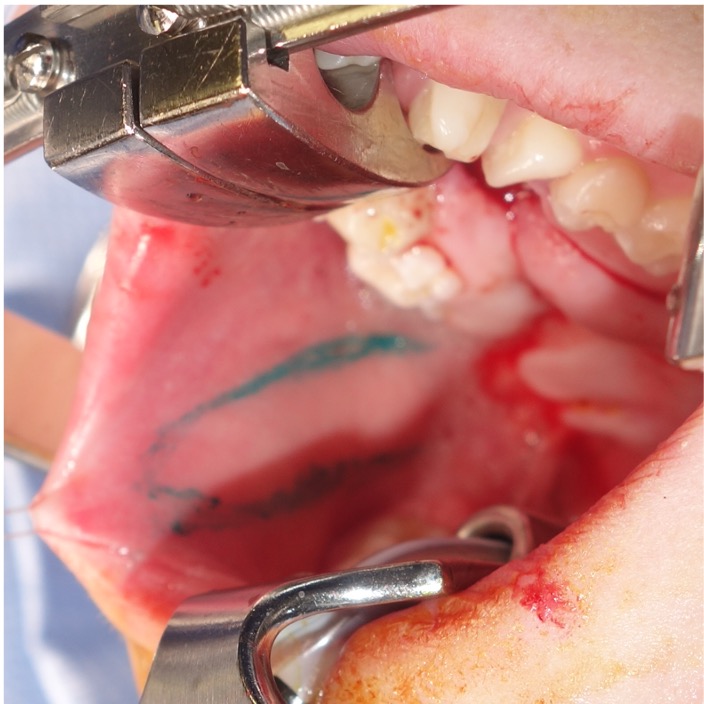

Figure 4. (A) A patient with a history of bilateral cleft lip and palate repaired elsewhere and 1 prior fistula repair attempt, presenting with a Type III fistula. (B) Markings for a conversion Furlow palatoplasty and left buccal myomucosal flap (BMMF). (C) Intraoperative view following flap elevation and inset, with the BMMF passed behind the dentition without occlusal impingement. (D) Healed flap, with division and inset planned for a future procedure.

The use of posteriorly based BMMFs for primary and secondary palatoplasties has gained popularity in recent years following the publications of Robert Mann.55,63 In Mann’s buccal flap palatoplasty procedure, the velum is lengthened and the levator veli palatini is repositioned by cutting the velum free of the posterior hard palate.55 The resulting nasal and oral lining defect is filled with bilateral BMMFs (one side is used for nasal lining and the other is utilized for oral lining).55 In many cases of fistula repair, the periphery of the fistula may be incised circumferentially to recruit sufficient oral lining to facilitate primary closure of the nasal lining (Figure 4A and B). In these cases, a greater oral defect is created, necessitating a local-regional flap for oral lining; s unilateral BMMF may be sufficient (Figure 4C and D).

Approximately 1 cm anterior to the pterygomandibular raphe, the main neurovascular bundle of the buccinator may be encountered, which must be carefully preserved for flap viability.30 The flap may be designed as a pedicled or island flap.29,40 Both can pivot and rotate up to 180 degrees, allowing for versatile inset options. However, to improve mobility, the mucosa at the flap base can be divided from the underlying muscle to create an island flap after the buccal artery has been identified and preserved.40,62 The island flaps can also be tunneled under the pterygomandibular ligament to avoid the occlusal plane.30,40 In our series of cases, islandization has not been necessary. Typically, adequate mobilization has been achieved, and dissection may be terminated at the retromolar trigon without identification of the buccal artery. The mucosal and submucosal pedicle may be preserved to reduce tension, minimize the risk of pedicle injury, and optimize venous drainage via the submucosal plexus. For posterior fistulas and in younger children, the pedicle can typically be passed behind the dentition without impingement across the occlusal plane (Figure 3A-C). In patients where the secondary molars have erupted, particularly the second molar, the chance of occlusal trauma to the pedicle may be higher. A contralateral bite block should be considered to prevent excessive mouth closure and protect the pedicle (Figure 3D-F). The patient should return to the operating room 2 to 4 weeks later for division and inset of the flap. When occlusal trauma is not a concern, division, and inset can be deferred or delayed until the time of another planned procedure.